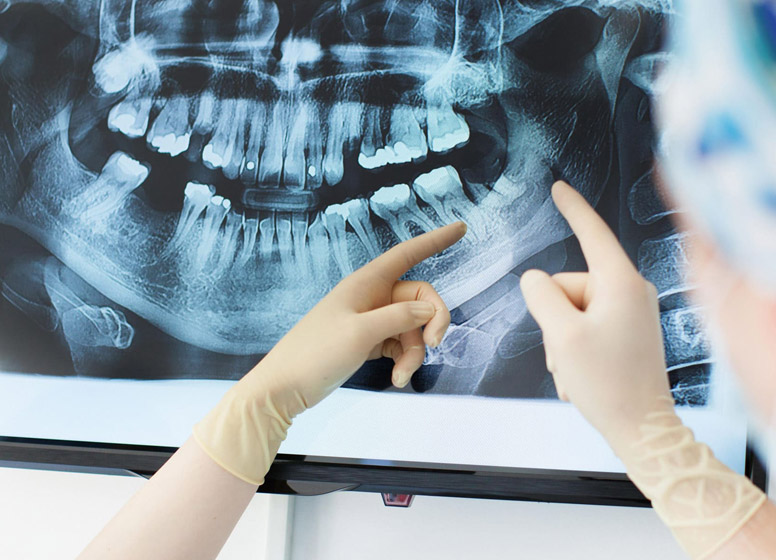

Radiografia digitală retroalveolară dentară este o radiografie digitală care se realizează la unul, maxim doi dinţi. Această radiografie permite medicului stomatolog să vadă în detaliu coroana şi rădăcina întregului dinte, la dimensiuni reale. De obicei această radiografie este indicată când se face un tratament endodontic (se scoate nervul) sau pentru o rezecţie apicală (operaţia rădăcinii dintelui).